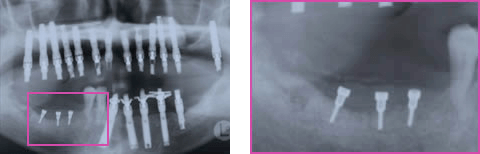

インプラント治療を希望し来院され、全顎的に高度の骨吸収を認めました(図1)。術前のCTデータをSimplantsにより3D構築し診断・計測したところ、下顎左側臼歯部の歯槽骨頂-下歯槽菅距離は第一第二大臼歯部で約9mmと近接、(図2)また、同部のハンスフィールド値からは歯槽頂部における皮質化の昂進を認めました(図3)。インプラント埋入には垂直的な骨高径獲得が必要不可欠であることから、vertical ridge augmentationを予定すると共に再生すべき垂直的骨量が約8mmであること、および同部の骨質から難易度の高さが予想されます(図4)。

術後13週時のパノラマX線写真では予定した骨高径が得られており、移植骨と母床骨との境界は不明瞭でした(図8)。術後24週時のX線所見では予定した骨高径が得られており(図9)、翌週に同部にインプラントを4本埋入、造成した骨には豊富な血流が認められ、骨質は比較的硬く初期固定は十分に得られました(図10)。インプラント埋入後3ヶ月時にはオステオインテグレーションの獲得を確認し、現在プロビジョナルレストレーションにて機能負荷を開始しているが経過は良好です(図11)。

長期間かけて吸収しかつ高度に皮質化した下顎遊離端欠損部におけるvertical ridge augmentationは難易度の高いケースと考えられます。このような症例に骨形成の促進が期待される超音波治療器を応用した結果、予定した骨高径の獲得および、臨床的に良質な骨の再生が認められ、インプラントによる機能回復が可能となりました(図12)。一般的に、vertical ridge augmentationは骨質、部位、個体差等の条件にも左右されますが臨床上約4mmが限界と報告されています。その理由の一つとして、移植骨部の周囲および内部における新生毛細血管の再生と同部の血流の再開が早期に行なわれ、それらに伴って移植骨部は一時的な吸収機転を経ますが、その体積を減ずる前の早期に骨リモデリングを開始する必要性がある為、量的限界が生じると考えられます。したがって今回のケースではmini screwによる高径の維持に加え、超音波刺激により局所における血流量の増加と細胞に対する適度な刺激により代謝活性の促進が行なわれ、5〜7mmの骨高径を獲得し良好な結果が得られたと推測いたします(図13)。

図1:初診時パノラマX線写真

図6:1回目GBR後36week 移植骨の吸収

下顎左側インプラント埋入前

図8:下顎右側臼歯部 再GBR後 13week

超音波治療応用後

中央部も境界不明瞭、近心部新生骨陵(+)

図9:下顎右側臼歯部 再GBR後 6M

超音波治療応用後

図12:術前